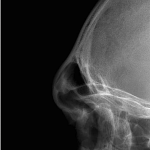

People considering custom jawline implants tend to ask a consistent set of questions. These generally fall into four categories: outcomes, safety, process, and recovery. What are custom jawline implants? Custom jawline implants are patient-specific implants designed from a 3D CT scan of your face. Unlike standard implants, they are digitally created to match your exact Read More…